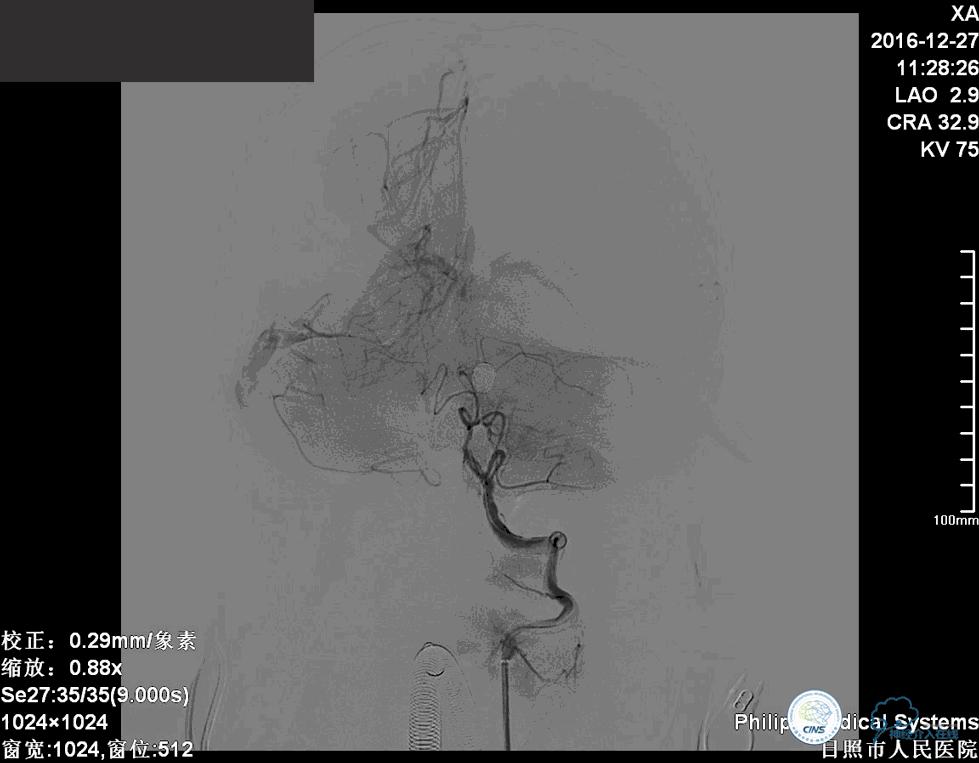

确诊:基底动脉顶端宽颈未破裂动脉瘤,动脉瘤大小约6mm×9mm,瘤颈约4毫米。

对于这个动脉瘤的介入治疗措施,包括球囊辅助弹簧圈栓塞介入治疗、支架辅助弹簧圈栓塞介入治疗、双微导管技术弹簧圈栓塞介入治疗。

这个病例我们采取了双微导管技术弹簧圈栓塞治疗。

这个动脉瘤是一个宽颈动脉瘤,动脉瘤的瘤颈和双侧的大脑后动脉关系比较密切。在进行栓塞治疗的时候要避免弹簧圈对双侧大脑后动脉以及小脑上动脉堵塞。

我们将两个微导管分别送入动脉瘤腔内,其中一个塑为u型,一个直头。两个微导管,一个位于动脉瘤较深的部位,1个位相对较浅的部位,交替进行栓塞。